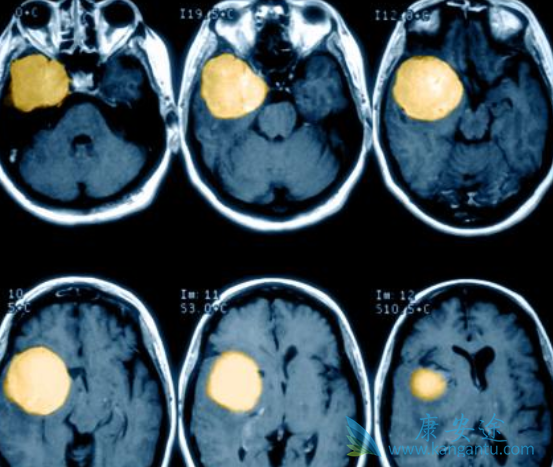

绝大多数脑膜瘤患者可通过手术、放疗或两者联合治疗获得满意的疗效。但仍然有不少患者脑膜瘤复发,这类脑膜瘤称之为手术和放疗难治性脑膜瘤(以下称为难治性脑膜瘤)。针对此病一直以来没有理想的药物可供选择。索坦(sunitinib)是一种口服的酪氨酸激酶抑制剂。体外实验证实,它可干扰脑膜瘤的增殖,而且在复发脑膜瘤中上调更明显。

一项关于索坦在治疗手术及放疗难治性非典型(II级)和间变型(III级)脑膜瘤的单组、多中心临床二期试验的结果,难治性脑膜瘤患者通过应用索坦可获得超出预期的疗效,36例患者肿瘤的6个月平均无进展率达42%。其中,1例死亡、3例颅内出血和11例因该药的毒副作用停止用药。

而在265例难治性脑膜瘤患者中应用羟基脲、替莫唑胺、环磷酰胺、长春新碱、贝伐单抗和伊马替尼等细胞毒性药物治疗,WHOI级脑膜瘤患者肿瘤6个月无进展率加权平均数29%,非典型和间变性脑膜瘤患者肿瘤6个月无进展率加权平均数26%,由此可见索坦(sunitinib)的疗效优于其它化疗药物。